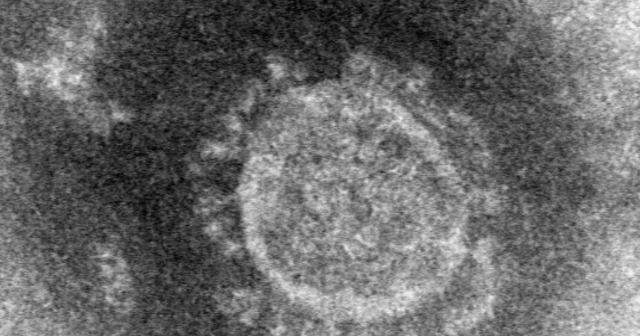

新型コロナウイルスの正式名称は?